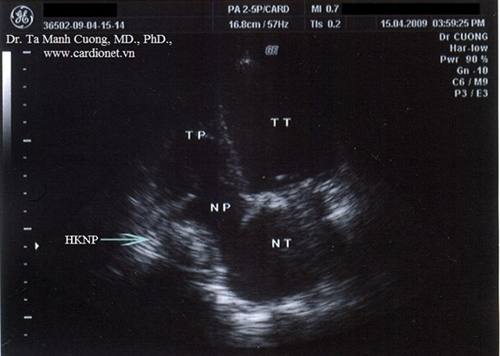

Hình ảnh huyết khối nhĩ phải ở một bệnh nhân van tim nhân tạo đang dùng thuốc chống đông AVK với INR = 2,5...

(CardioNet.VN) - Nam 27 tuổi, mang van hai lá và van động mạch chủ cơ học, rung nhĩ. Đang được dùng thuốc chống đông loại kháng vitamin K (AVK) với INR = 2.5. Làm siêu âm tim kiểm tra thường quy thấy các van tim nhân tạo hoạt động bình thường. Khi kiểm tra buồng nhĩ phải thì thấy có hình ảnh huyết khối...

Khi phóng to hình ảnh, huyết khối được nhìn thấy rõ hơn trong nhĩ phải.